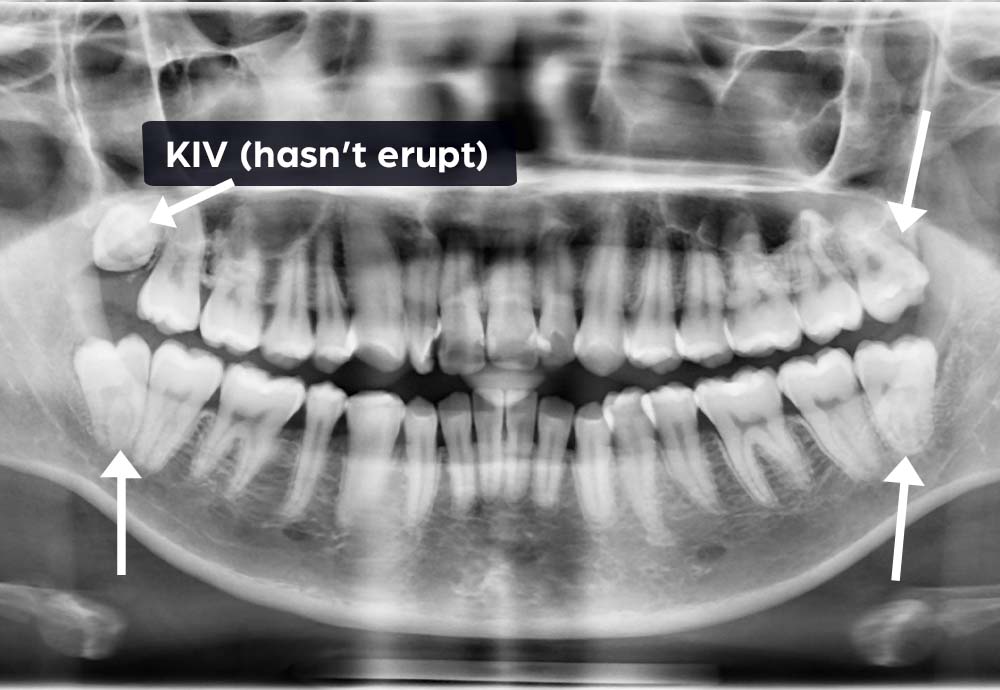

Some lower wisdom teeth can be close to the inferior alveolar nerve (which gives feeling to your lip & chin).

In rare cases, this may cause temporary symptoms such as:

Wisdom tooth removal is generally safe, but like any surgical procedure, there are some risks such as nerve irritation and infection.

In rare cases, lower wisdom teeth may be close to a nerve, which could cause temporary numbness. To improve safety, we use Piezo-assisted surgery and laser disinfection, which help protect nearby tissues and support faster healing.